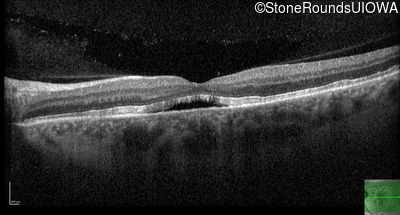

Optical Coherence Tomography - Right - 20/25

Exemplar / OCT Stack

OCT Stack